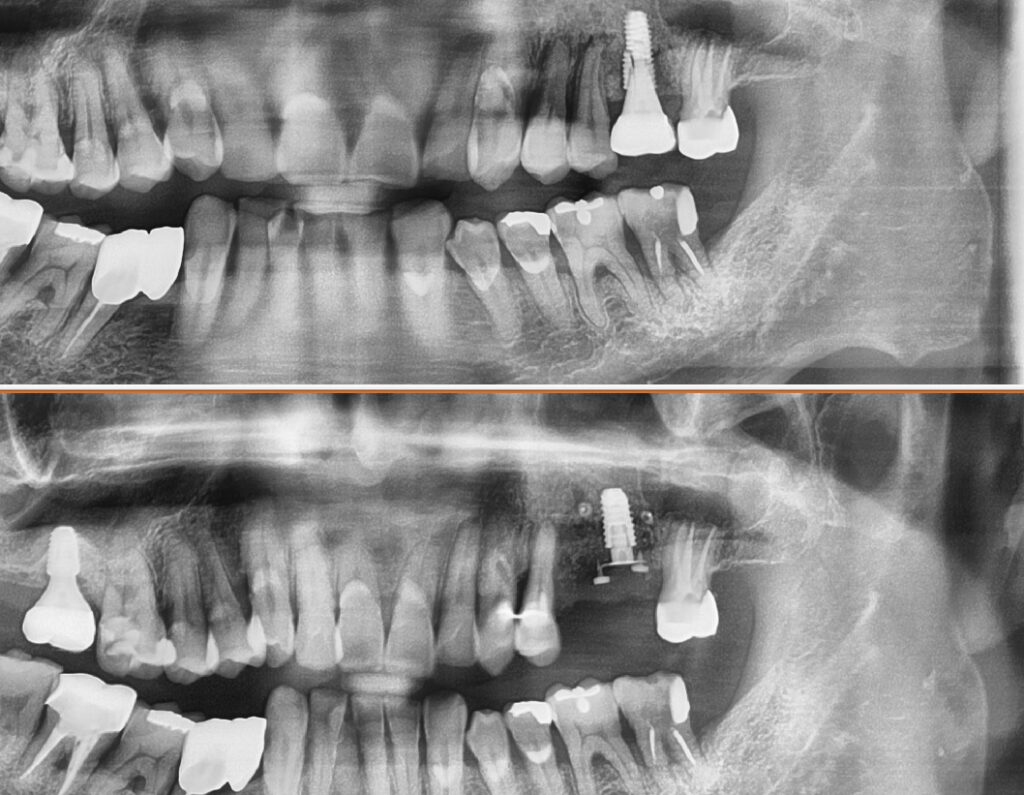

그렇다면 이런 케이스의 변화는 어떻게 되었을까요

상악동 거상술+점액종 제거술을 본원에서 시행한 후 완료된 사진입니다

가운데 임플란트에 비하여 훨씬 길고 안정되게 식립한 것을 볼 수 있습니다

한가지로 정리하면요

이정도의 상악동 거상술이면 안정되고 오랜 수명을 생각할 수 있을 듯 합니다